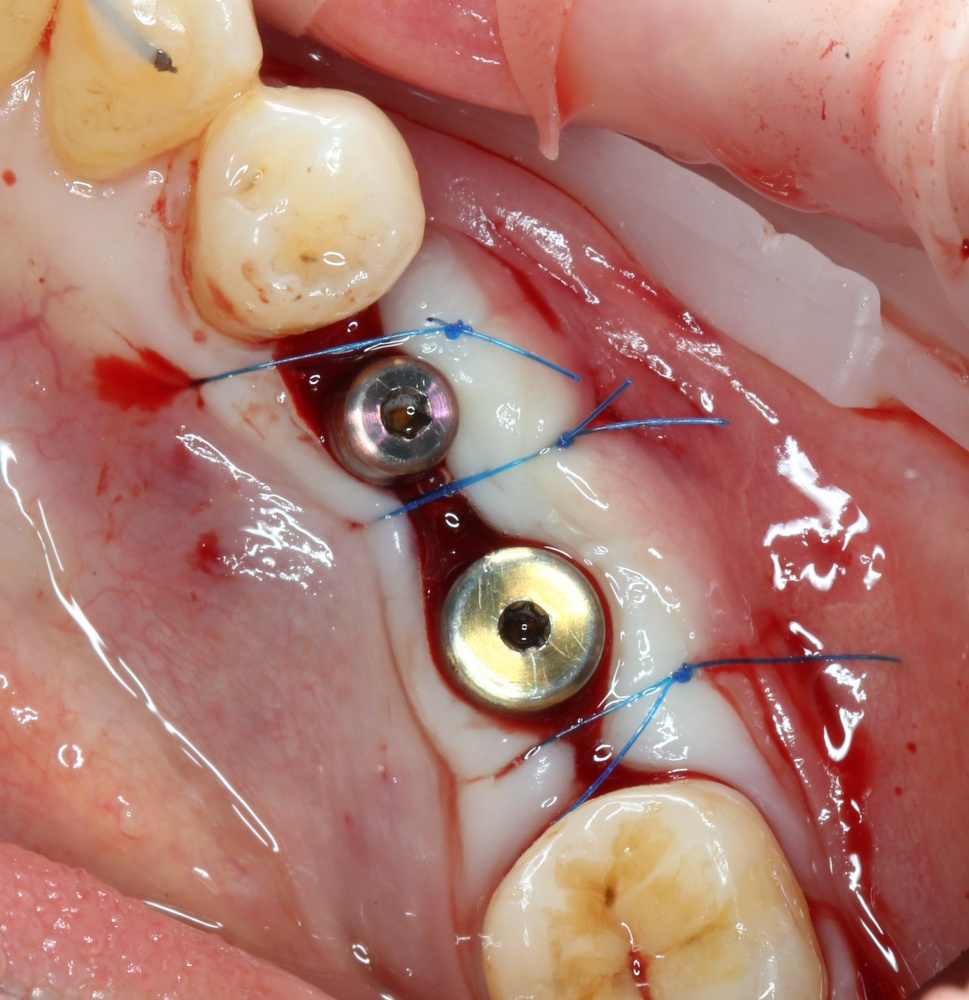

Теперь делаем разрез и открываем импланты:

A09A6620 (2) A09A6621 (2)

На фотографиях хорошо видно, какие изменения произошли с областью операции за четыре месяца. Пересаженный костный блок интегрировался настолько хорошо, что частично заросли заглушки имплантов. Такое нередко происходит, именно поэтому в подобных случаях я предпочитаю импланты с конической ортопедической платформой — их легче открывать.

Нам остается просто поставить формирователи десны:

A09A6628 (2) A09A6629 (2)

и подождать, пока вокруг них сформируется плотная слизистая оболочка. Потом мы направляем пациента к ортопеду для протезирования.